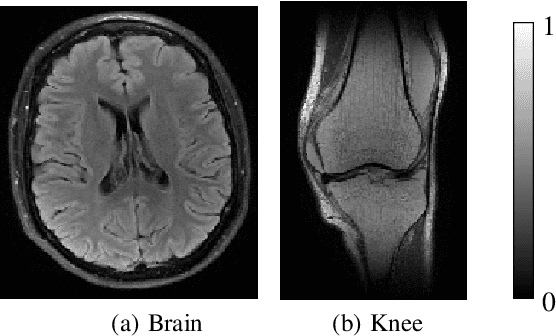

Abstract:In compressed sensing (CS) MRI, model-based methods are pivotal to achieving accurate reconstruction. One of the main challenges in model-based methods is finding an effective prior to describe the statistical distribution of the target image. Plug-and-Play (PnP) and REgularization by Denoising (RED) are two general frameworks that use denoisers as the prior. While PnP/RED methods with convolutional neural networks (CNNs) based denoisers outperform classical hand-crafted priors in CS MRI, their convergence theory relies on assumptions that do not hold for practical CNNs. The recently developed gradient-driven denoisers offer a framework that bridges the gap between practical performance and theoretical guarantees. However, the numerical solvers for the associated minimization problem remain slow for CS MRI reconstruction. This paper proposes a complex quasi-Newton proximal method that achieves faster convergence than existing approaches. To address the complex domain in CS MRI, we propose a modified Hessian estimation method that guarantees Hermitian positive definiteness. Furthermore, we provide a rigorous convergence analysis of the proposed method for nonconvex settings. Numerical experiments on both Cartesian and non-Cartesian sampling trajectories demonstrate the effectiveness and efficiency of our approach.

Abstract:Model-based methods play a key role in the reconstruction of compressed sensing (CS) MRI. Finding an effective prior to describe the statistical distribution of the image family of interest is crucial for model-based methods. Plug-and-play (PnP) is a general framework that uses denoising algorithms as the prior or regularizer. Recent work showed that PnP methods with denoisers based on pretrained convolutional neural networks outperform other classical regularizers in CS MRI reconstruction. However, the numerical solvers for PnP can be slow for CS MRI reconstruction. This paper proposes a preconditioned PnP (P^2nP) method to accelerate the convergence speed. Moreover, we provide proofs of the fixed-point convergence of the P^2nP iterates. Numerical experiments on CS MRI reconstruction with non-Cartesian sampling trajectories illustrate the effectiveness and efficiency of the P^2nP approach.

Abstract:Model-based methods are widely used for reconstruction in compressed sensing (CS) magnetic resonance imaging (MRI), using priors to describe the images of interest. The reconstruction process is equivalent to solving a composite optimization problem. Accelerated proximal methods (APMs) are very popular approaches for such problems. This paper proposes a complex quasi-Newton proximal method (CQNPM) for the wavelet and total variation based CS MRI reconstruction. Compared with APMs, CQNPM requires fewer iterations to converge but needs to compute a more challenging proximal mapping called weighted proximal mapping (WPM). To make CQNPM more practical, we propose efficient methods to solve the related WPM. Numerical experiments demonstrate the effectiveness and efficiency of CQNPM.